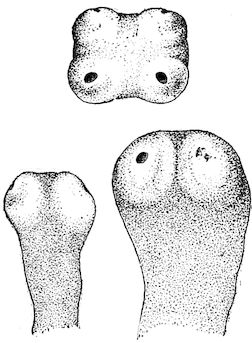

Fig. 4.—Deformity of the face in the horse shown in Fig. 2.

The flat bones are particularly liable to this change, which is common to domesticated animals. The bones of the head are the first to suffer; later those of the pelvis. The lower jaw becomes swollen, particularly about the centre of the branches which may attain three, four, or five times, their normal thickness.

The depression in the submaxillary space disappears. The upper jaw undergoes similar changes, becoming deformed and thickened until the cavities of the sinuses and the hollow appearance of the palate are lost, while the face is so changed that it cannot be recognised as that of a horse, goat, etc.

The molar teeth are almost buried, their tables alone being visible at the bottom of a depression, the edges of which rise above the neighbouring parts (pig).

Mastication is clearly impossible, the jaws appear paralysed, the muscles powerless, and only swallowing is possible, a fact which explains why life is only prolonged to this stage in animals which can be fed with a spoon or bottle (pigs and goats). The bones of the cranium, although greatly changed in texture, are always less deformed than those of the face.

Fig. 7.—Osseous cachexia: softening of the maxillæ.